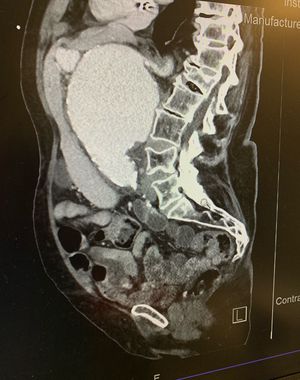

84 y/o patient presented to the ED c/o back pain and mild epigastric pain. CT abdomen revealed a 9.8 cm AAA.